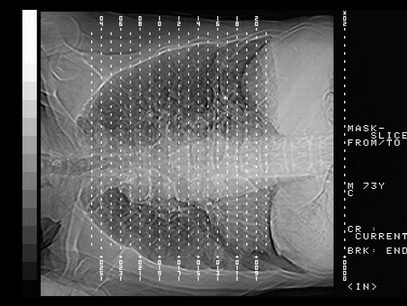

标题: CT10820:男,73岁,病史肺TB,现病史肺炎,直肠CA术后 [打印本页]

双肺间质改变,依据病史双肺多发结节灶考虑转移,少量胸水.

1.两肺结核.2.两肺多发转移瘤.3右侧少量胸腔积液4.主动脉钙化.

双肺多发结节及条片状致密影,右侧少量胸腔积液。临床:直肠ca术后,肺tb病史。综合考虑:1 双肺转移!2 继发性肺结核合并感染!

此人病史较复杂,原有肺结核,直肠癌术后。肺部病灶形态亦呈多形性。因此,不可仅以一种病来解释肺部的病变。双肺多发的类圆形结节灶,结合病史还是首先考虑转移瘤,而双肺其余病灶还需结合化验室检查,结核或肺部感染在无其它检查资料的情况下不好排除。还是那句话----放射科医生不是开照像馆的,我们也是医生,看片一定要多结合临床及其它检查资料。要当一名合格的放射科医生,并不比当一名临床医生容易,我们可别把自已不当医生看。

两肺多发结节影,并见滋养动脉与其相连,考虑 两肺转移. 右侧胸腔积液考虑胸膜转移.

左肺上叶下叶背段,右肺中下叶见多发斑片状、条索状高密度影,兵变周围小结节影形成“树芽”样改变。 左肺上叶舌段近前胸壁处及右肺中叶内侧段见结节影。右侧胸膜腔内见液体密度区。纵隔内未见明确增大淋巴结。考虑左肺上叶舌段近前胸壁处及右肺中叶转移瘤可能性大。两肺继发型肺结核。右侧胸腔积液。

还有心包少量积液。